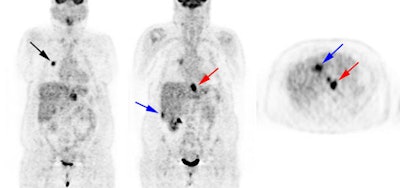

Response to therapy: This is the patient shown in the case above with progressive dysphagia and a large distal esophageal mass with gastrohepatic ligament adenopathy. Note the decreased uptake within the primary mass (arrowhead) and gastrohepatic nodes following initiation of radiation therapy. However, new uptake can be seen in two lymph nodes (black arrows) which were not identified prospectively on post-therapy CT imaging (white arrows on CT). The findings are concerning for metastatic disease and the patient went on to receive additional chemotherapy with subsequent resolution of the nodal uptake. |